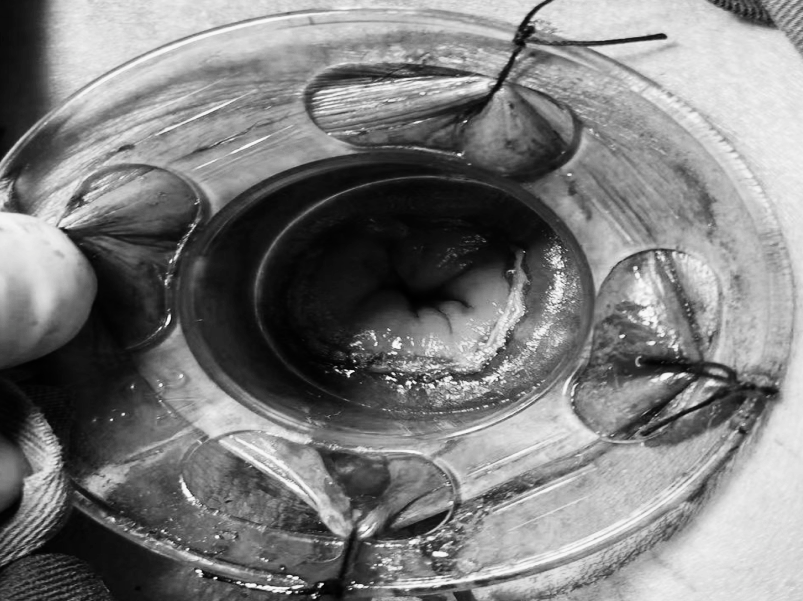

8月27日,贵州航天医院第75次晨读会由我院柔性引进的知名肛肠外科专家高大勇教授作学术交流,他以“肛肠科常见病浅谈”为题,系统讲解了痔疮、肛裂、肛周脓肿等常见肛肠疾病的症状表现、潜在风险及相应治疗方式,为医院带来了前沿医疗理念与技术,有效提升了医务人员对肛肠疾病的早期识别与诊疗水平,也为学科建设、临床诊疗能力的长效提升奠定了坚实基础。 贵州航天医院 普外科专家简介 高大勇 普外科(肛肠外科)学科带头人、名誉主任,主任医师、教授 临床擅长:对中西医结合诊治肛肠学科各种常见病、多发病及疑难杂症等具有丰富的临床经验。 原遵义市第一人民医院(遵义医科大学第三附属医院)、遵义市中医院肛肠科主任。中华中医药学会肛肠分会常委,全国中医肛肠学科名专家,中国健康促进与教育协会肛肠分会常委,中国康复医学会肛肠疾病康复专业委员会常委,中国民间中医医药研究开发协会肛肠分会副秘书长,中国医师协会中西医结合肛肠医师专业委员会常委,国家二级心理咨询师,贵州省第一批中医名医工作指导老师,遵义市名中医,遵义市肛肠学会会长,遵义市肛肠质控中心名誉主任,遵义市中西医结合学会名誉会长,遵义市健康科普专家,原贵州省中西医结合学会肛肠分会副主任委员、贵州省中医肛肠质控中心副主任、遵义市医学会医疗鉴定委员会专家、遵义市卫生系列高评委。发表论文30余篇,主编和参编医学著作5本,主持省级科研课题2项、市级科研课题2项、院级科研课题1项。 梁   跃 中共党员,普外科党支部书记、主任,主任医师 临床擅长:对普外科各类肿瘤手术具有丰富的临床经验。 毕业于遵义医学院,遵义市医学会小儿外科学分会常务委员,遵义市肛肠协会理事,遵义市医学会核医学分会(第二届)委员会委员;荣获第三期“黔医人才计划”优秀学员称号;主持市级课题1项,完成省级课题1项,在国内各类刊物上发表论文10余篇。 钱科洪 民盟盟员,普外科副主任医师 临床擅长:从事普外科临床工作30余年,对各类普外科疾病的诊治、乳腺、甲状腺、胃十二指肠、结直肠等疾病及疑难杂症具有丰富的临床经验。 毕业于遵义医学院临床医疗系,2009年前往中山大学附属第一医院微创外科进修学习,在国内各专业期刊发表论文数篇。 贵州航天医院 普外科简介 基本情况 贵州航天医院普外科成立于1968年,前身属于航天部O61基地3417医院外一科,1998年3417医院、3427医院合并后更名为普外科,下设胃肠外科、肛肠外科2个亚专业科室,拥有在全市较为先进的专科设备和技术,是中国疝病专科联盟单位,贵州医科大学附属医院胃肠外科专科联盟单位。开放床位40张,配备医护人员21人。 专科特色技术 普外科致力于胃肠及肛肠疾病的外科临床诊治及科研,以腹腔镜微创外科技术为本,形成以快速康复治疗胃肿瘤、结直肠肿瘤、小肠肿瘤、直肠脱垂、肥胖病、急腹症、各类疝、痔、瘘等专科特色,同时注重胃肠疾病尤其是结直肠恶性肿瘤的基础研究和临床转化研究,总体诊断和治疗水平在区域同级医院居于领先水平。 开展手术:腹腔镜下胃癌根治术,腹腔镜下袖状胃切除术,腹腔镜下胃肠道间质瘤切除术,腹腔镜下结、直肠癌根治术,胃癌、结直肠癌的精准治疗,腹腔镜下小儿疝气、成人疝修补术,腹腔镜下阑尾手术,内痔的硬化注射治疗及痔疮的微创治疗:ATH、PPH、TST,直肠脱垂的各种手术治疗,难治性伤口VSD技术,鼻胃肠管、肠梗阻导管置入术,肛肠术后间歇性导尿技术,并引进了中医适宜技术,也为各种化疗患者提供输液港安装,提高患者就医体验。 腹腔镜下腹股沟疝 无张力修补术 腹股沟疝里金斯坦(Lichtenstein)手术 PPH微创术治疗环状混合痔 黏连性或炎性肠梗阻-肠梗阻导管 腹腔镜袖状胃切除 腹腔镜阑尾切除术 腹腔镜阑尾肿瘤切除术 腹腔镜下结肠癌根治术 科室诊疗范围 胃肿瘤、结直肠肿瘤、小肠肿瘤、肥胖症、各类急腹症、腹部外伤、腹壁疝、便秘、直肠脱垂、痔疮、肛瘘、肛裂等胃肠、肛肠外科疾病。 end